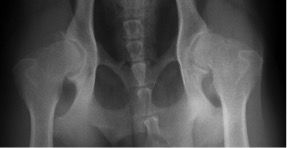

Bei der FCI-Methode werden Hunde je nach Rasse im Alter von zwölf bis 24 Monaten untersucht. Dabei werden die Patienten in Narkose mit gestreckten Gliedmaßen geröntgt, so dass die Oberschenkelknochen parallel zueinander liegen. Diese relativ unnatürliche Haltung ist die Grundlage zur Beurteilung des Grades der HD auf den Röntgenaufnahmen. Der Tierarzt beurteilt das Aussehen von Oberschenkelkopf und Hüftpfanne und deren Passform zueinander. Darüber hinaus misst er den sogenannten Norberg-Winkel, der bei einem HD-freien Hund 105 Grad und mehr beträgt. Auf diese Weise lassen sich fünf Schweregrade von A (HD-frei) bis E (schwere HD) der Hüftgelenksdysplasie unterscheiden.

Für das PennHIP® Verfahren werden drei Röntgenaufnahmen angefertigt:

Bei der Distraktionsaufnahme wird ein sogenannter Distraktor zwischen die Beine des Tieres gelegt. Wenn der Untersucher die Beine des Hundes gegen den Distraktor drückt, wird der Oberschenkelkopf aus der Hüftpfanne „herausgezogen“. Je weiter das möglich ist, desto lockerer ist die Hüfte und desto größer die Wahrscheinlichkeit, dass ein Hund an einer HD leiden wird. Das Maß für die Lockerheit des Hüftgelenks ist dabei der Distraktionsindex (DI).